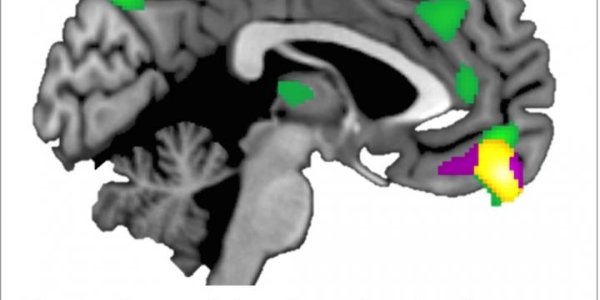

Brain Structure Varies With Trust Level

A recent study shows differences in brain structure according to how trusting people are of others. The psychologists used two measures to determine the trust levels of 82 study participants.…